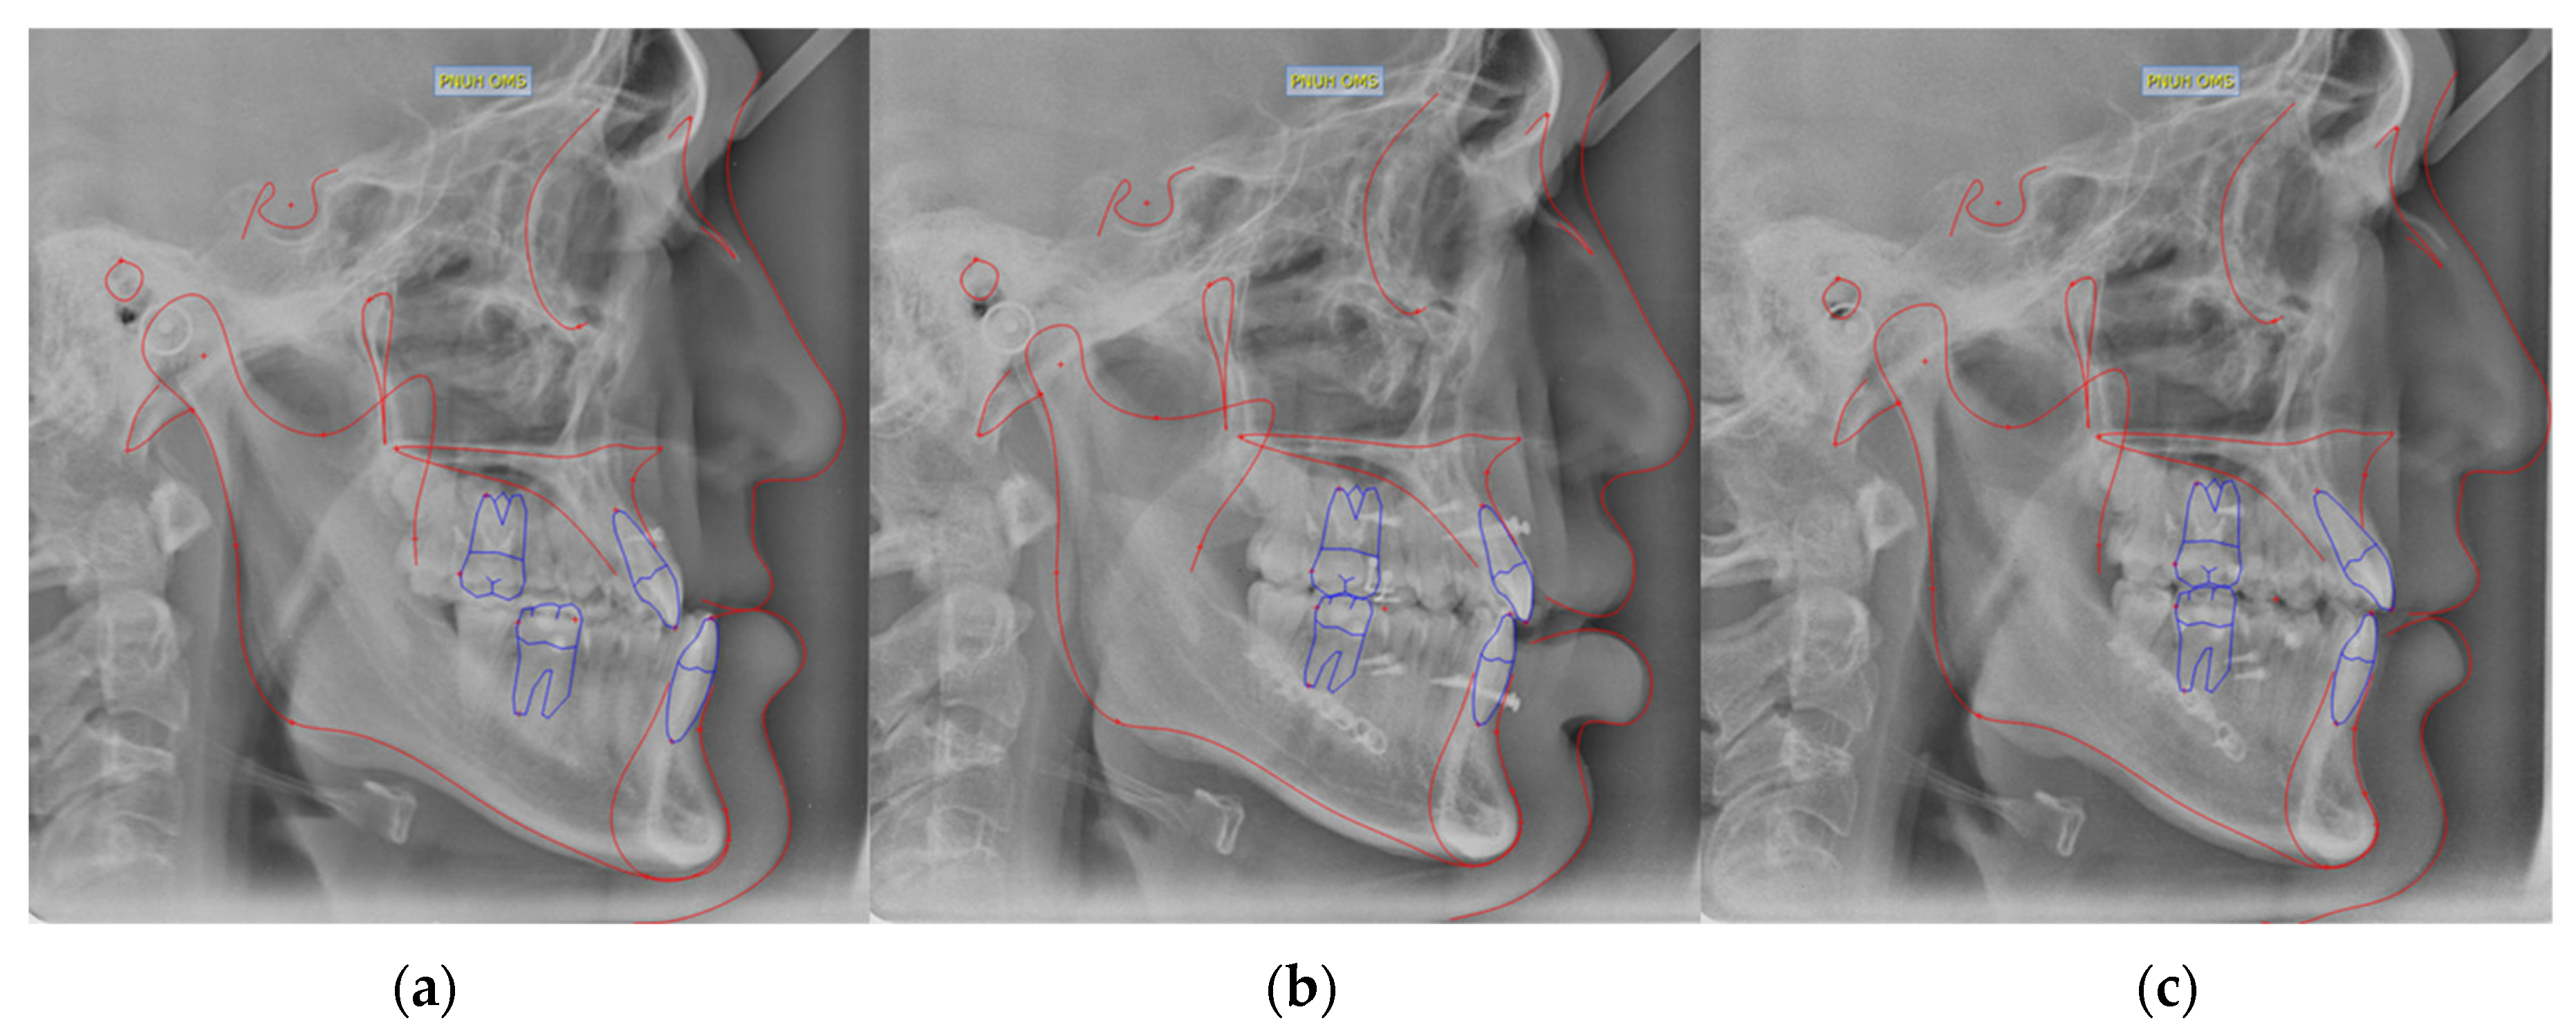

For all patients, cone beam computed tomography (CBCT), and lateral cephalometric radiographs were taken postoperatively on day 2 and month 6 to confirm skeletal changes (Figure 1 and Figure 2). Postoperative stability was evaluated and analyzed by measuring several measurement variables (L1 to NB, Pog. to NB, A-Pog., angle of facial convexity (AFC), SN vertical, and 0-merdian) (Table 1). The duration of each patient’s preoperative orthodontic period, the number of premolar extractions, and the number of impacted teeth were also compared and analyzed.

Figure 2. Orthognathic surgery patient with conventional fixed appliance. (a) Before surgery; (b) 2 days after surgery; (c) 6 months postoperative radiograph image. The bracket attached to teeth was not observed on radiographs.